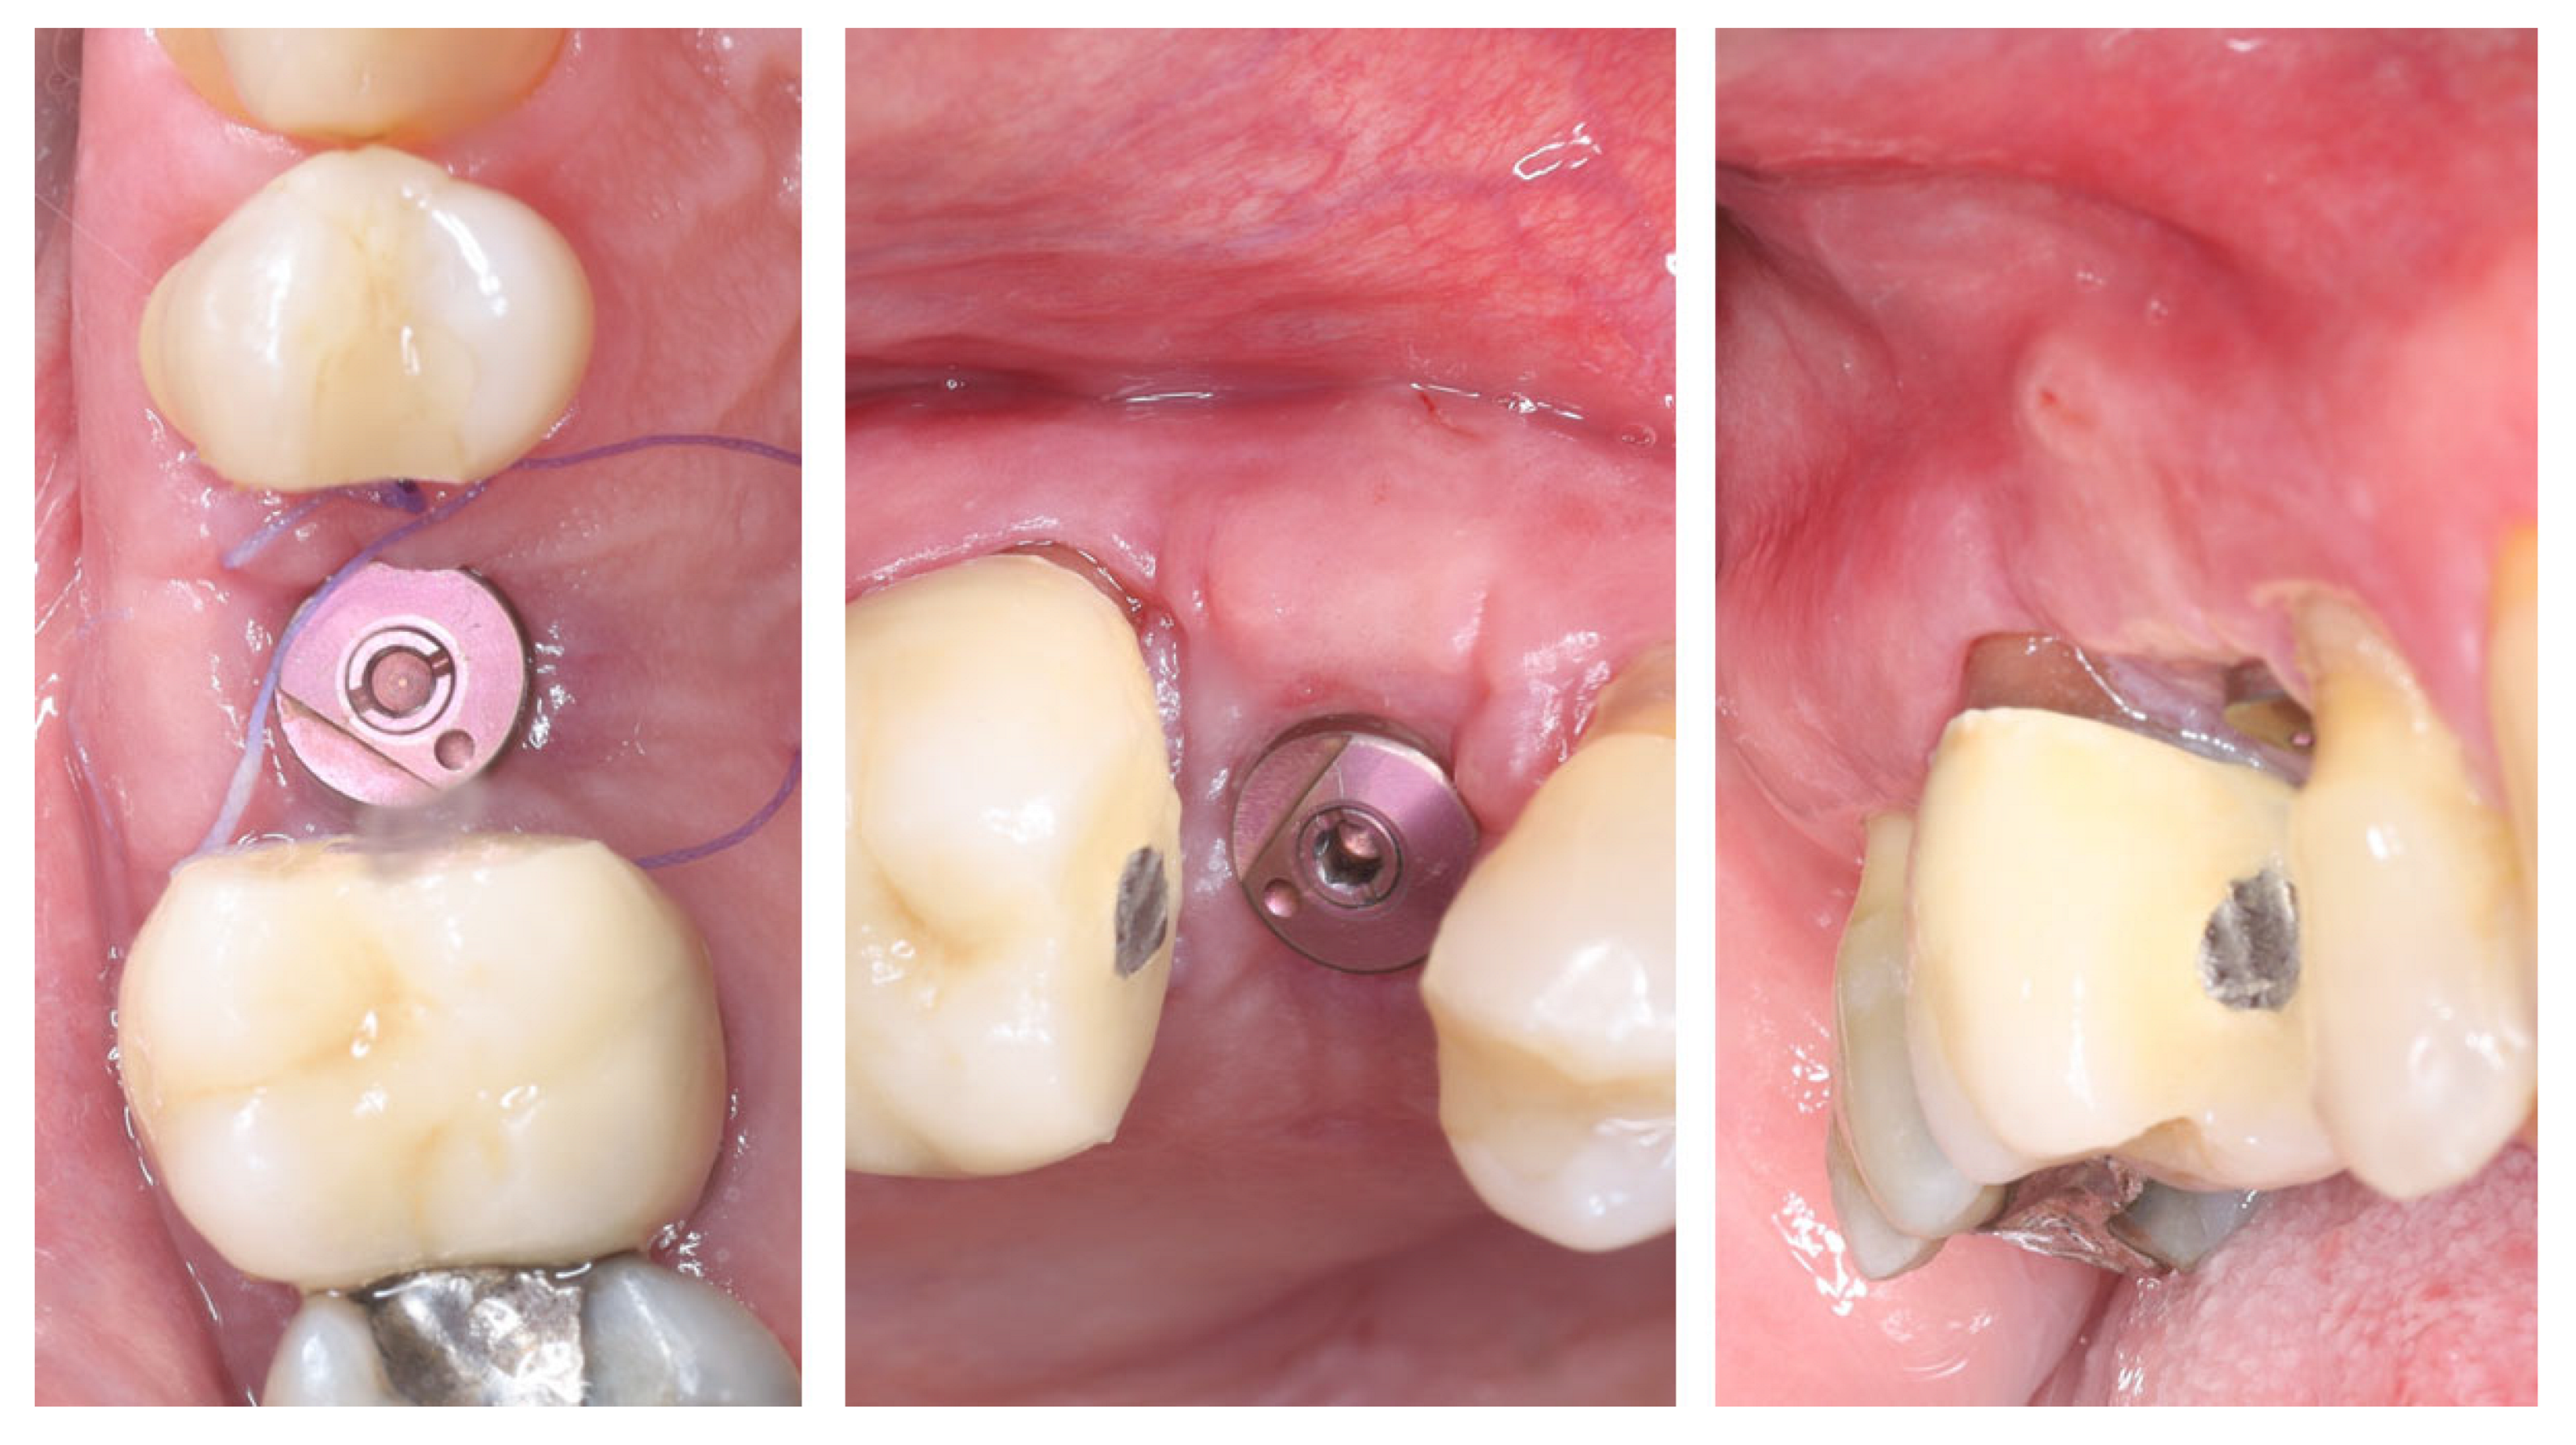

2. Materials and Methods—Clinical Case

| 1 | Baseline (Day 0) | 2.3 | 2.4 | Initial thin buccal tissue |

| 2 | 2 weeks post-op | Uneventful healing, stable mucosal margin | ||